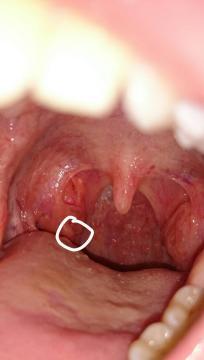

Dobrý deň, už dlhšiu dobu mám problém s prehĺtaním a nedávno som si všimla takýto výčnelok na mandli. Mám sa báť alebo to nič nie je ? Neviem čo to má byť. Mám mandlové kamene a neustály zápach z úst a biely povlak na jazyku. Už mi to vadí.

Dobrý den, fotografie není příliš zřetelná, ale nezdá se mi, že by tam bylo něco patologického. Na mandlích máte krypty (dírky) po čepích, mandle jsou mírně zvětšené, možná je zde chronická tonsilitida. Tou ale trpí hodně lidí. Zkusila bych výtěr z krku.